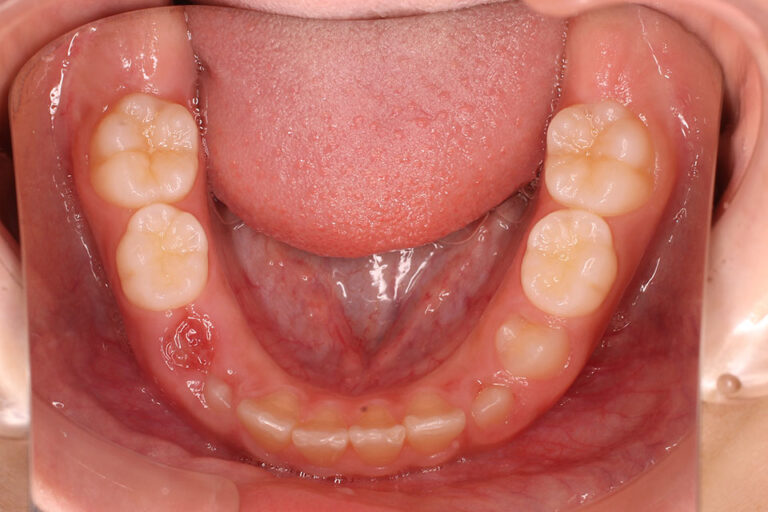

| 前歯の生え変わりの時期(小学校低学年)、他院で歯並びを指摘されたということで来院されました。

永久歯萌出スペース不足は軽度でしたが、上の前歯は前方(唇側)に強く傾斜、下の前歯は内側(舌側)に強く傾斜しており、前歯の咬み合わせは深く過蓋咬合です。 小児矯正で、過蓋咬合と叢生(がたつき)が初診時よりもひどくならない様に、下顎の成長促進と永久歯の萌出スペース確保を行いました。 永久歯が全て生えて(永久歯列完成)から本格矯正の治療になります。(中学1~2年生頃) 叢生量(がたつき量)と前歯の深い咬み合わせを減少させる事により抑制されていた下顎の前方への成長がありました。 小児治療後の本格矯正は、患者さんの希望もありましたので、非抜歯での治療となりました。 来院間隔は1~2カ月毎でしたので、治療期間が平均より長めです。 マルチブラケット 動的治療期間 3年0か月 がたつき(叢生)少ない状態からの非抜歯治療ですので、口唇の大きな変化はありませんが、 下顎が成長した分は良くなったように見えます。 | ||